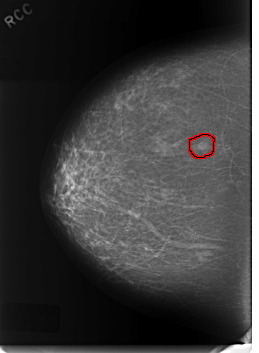

FILE: C_0331_1.RIGHT_CC.OVERLAY

TOTAL_ABNORMALITIES 1

ABNORMALITY 1

LESION_TYPE MASS SHAPE OVAL MARGINS CIRCUMSCRIBED

ASSESSMENT 3

SUBTLETY 5

PATHOLOGY BENIGN

TOTAL_OUTLINES 1

BOUNDARY